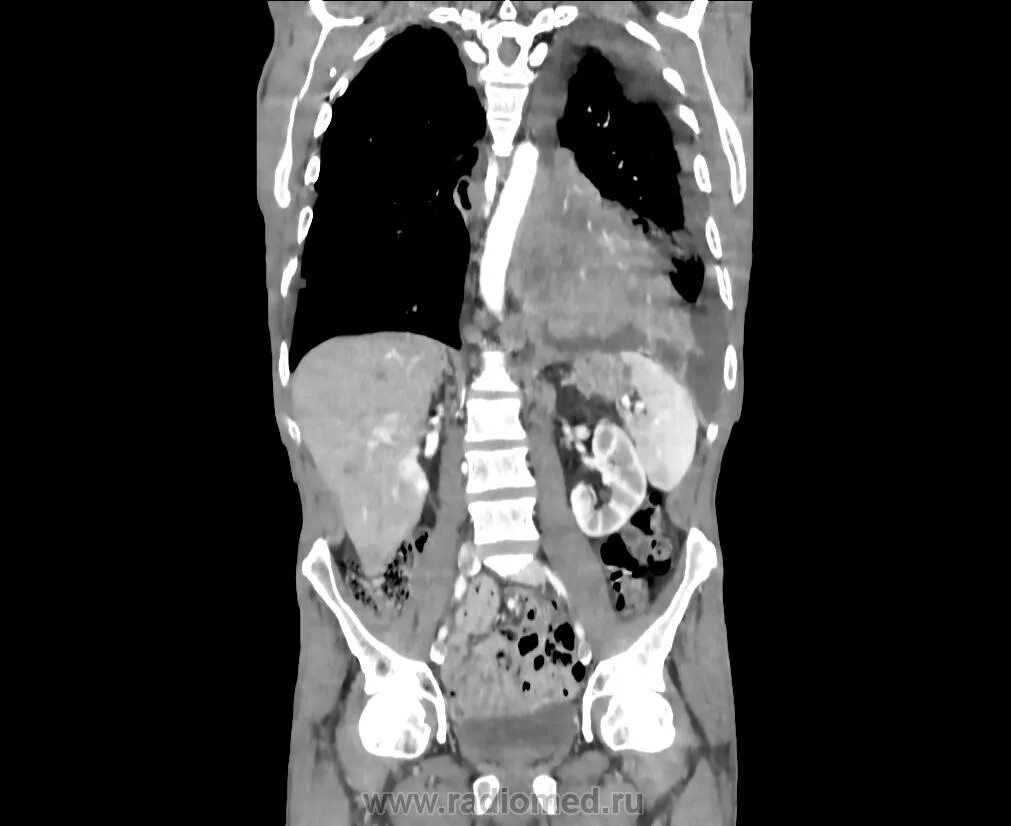

4 стадия метастазы легких